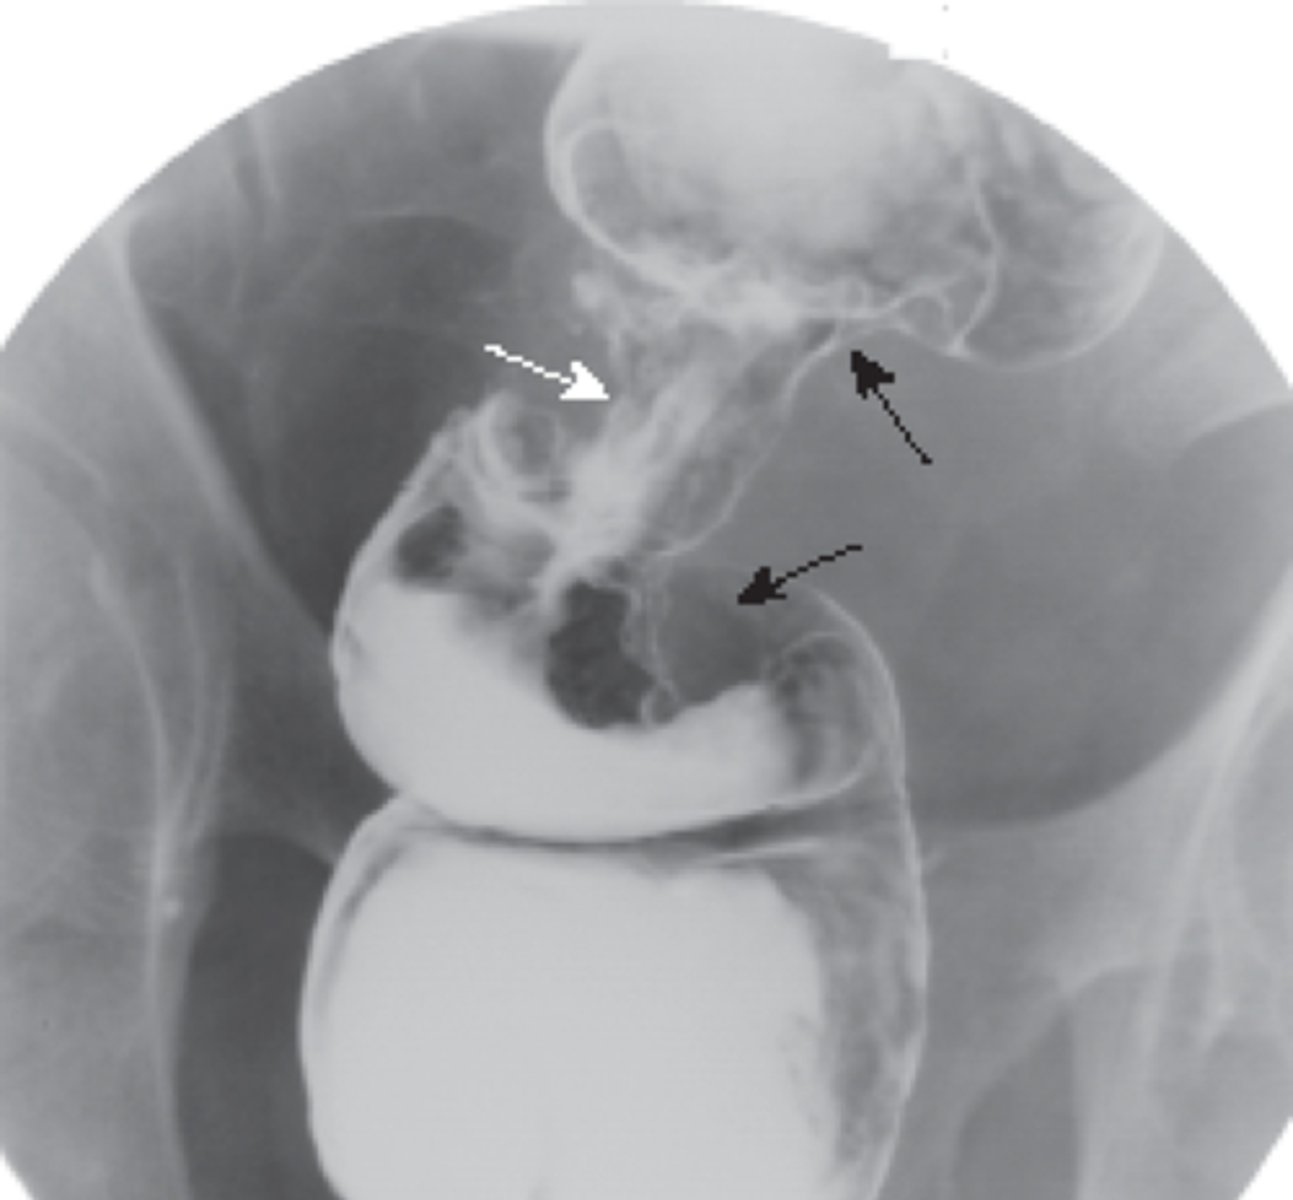

Ulcerative colitis